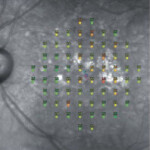

iCare MAIAは、眼底画像撮影機能を備えた自動マイクロペリメーター(Fundus Perimetry)です。高品質な眼底LED共焦点スキャナーの自動網膜追尾により、眼球運動を正確かつリアルタイムに補正します。この先進技術は網膜感度・固視分析に加え、網膜のTrueColorおよびIR共焦点撮影画像も提供します。

4段階固定の簡易ストラテジーおよび4-2全閾値ストラテジーによるマイクロペリメトリー検査と、機能の進行をモニタリングするフォローアップ検査が可能です。

各検査では網膜感度と固視分析を表示します。フォローアップ検査では、ベースラインを解剖学的位置に設定し検査します。